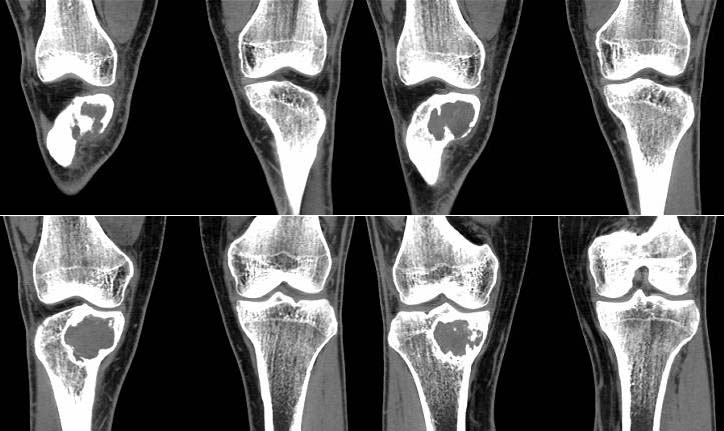

男,38岁,右膝下方剧烈运动后疼痛1年3个月,疼痛加重并局部隆起1个月。查体见轻度跛行,右胫骨近端前内侧轻度隆起,隆起部位压痛明显,皮温略有增高。右膝关节活动度基本正常,麦氏征、膝关节抽屉试验(-)。

胫骨近端、骨骺前内侧见局限性骨质破坏,边缘硬化明显,其间有少许残陈骨,边缘增生硬化,并可见嵴状突起,皮质部分断裂,无骨膜反应。

征象:胫骨上干骺端偏心性类圆形骨质破坏,边缘硬化,可见病理性骨折,内有残留骨嵴。未见明显骨膜反应及软组织肿块。

1. gct多发生于骨骺部,关节面易侵犯。

2. gct常横轴较大。

3. gct膨胀明显,如“皂泡”样,但病理性骨折少见。

4. gct硬化边少见,但有骨间隔或分房。